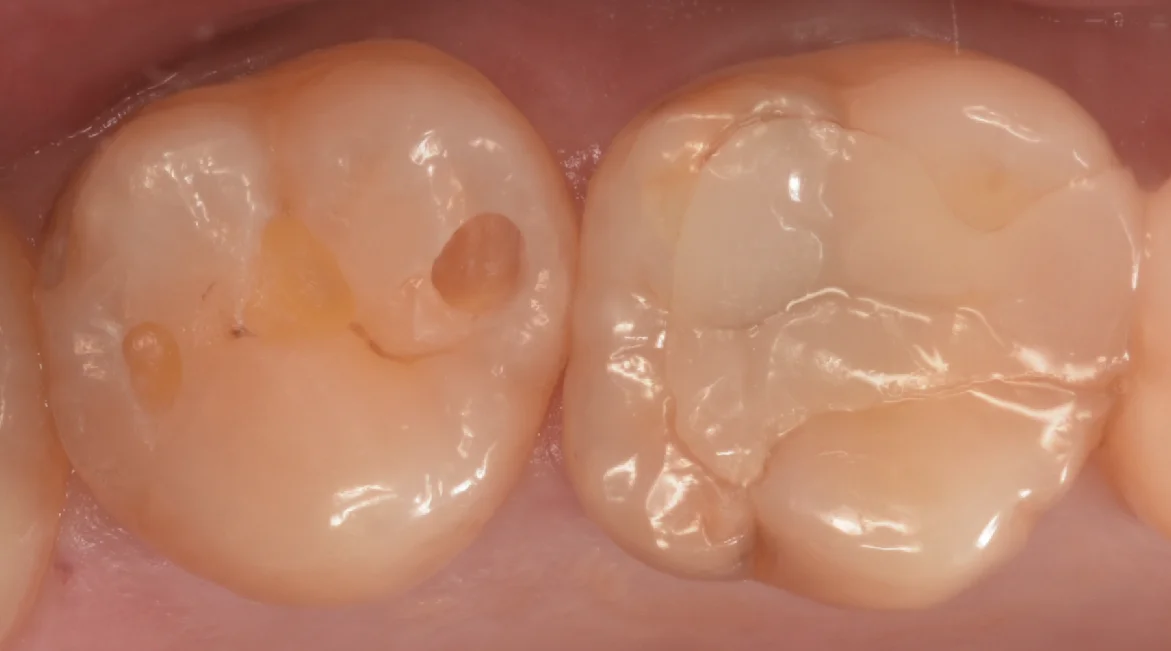

軽く虫歯を見えやすくしたのがこちらになります。

中心の白い詰め物のところはそこまで虫歯ではなかったですね。

右側の方の虫歯が一番大きい状態です。

左側の虫歯は非常に小さい状態でしたね。